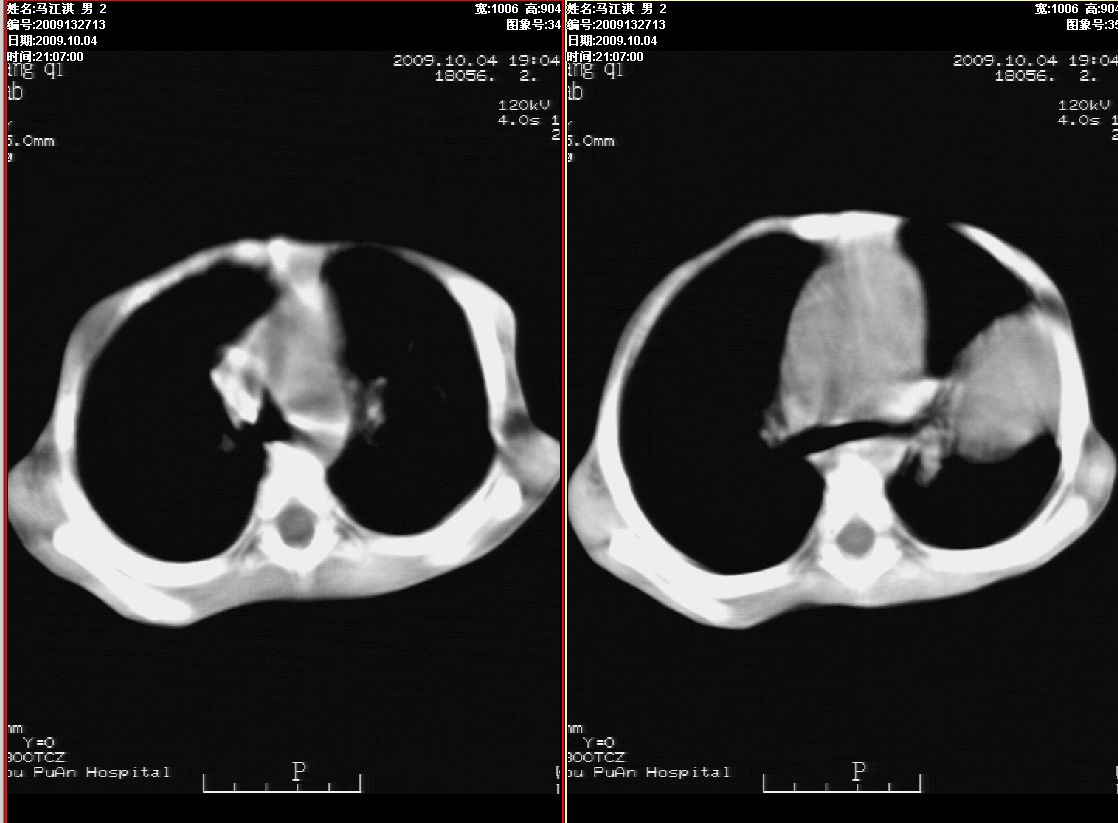

右肾巨大囊性占位病变,其内密度不均,正常肾结构消失,肝脏,肾上腺及肠管等受压移位。双肺内多发大小不等的结节及块状影。考虑右肾母细胞瘤伴双肺多发转移。

肾母细胞瘤(wilms),系儿童最常见的恶性肿瘤,好发于3岁以下儿童,瘤体较大,主要由胚胎性肉瘤样细胞和上皮样细胞构成,临床以腹部肿块;血尿和高血压为主要体征。

ct表现:密度不均匀的大肿块存在;出血和坏死。与神母鉴别点:wilms易向颅脑转移,而神母易往肺转移。

ct表现:密度不均匀的大肿块存在;出血和坏死。与神母鉴别点:wilms易向肺转移。而神母易往颅脑转移.